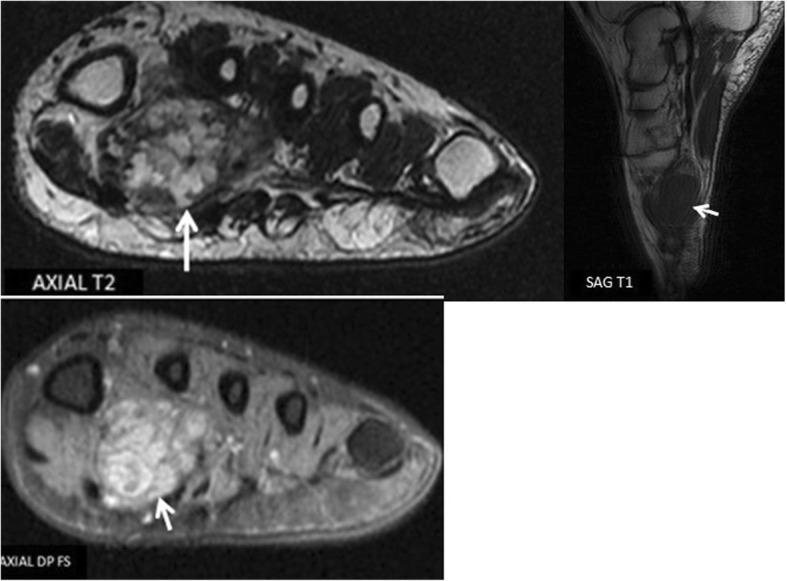

We report a case of a plantar intramuscular hemangioma in 25-year-old patient with a history of percutaneous therapy. Patient had undergone intralesional sclerotherapy 3 years prior to his admission with persistent pain on weight bearing activities.MRI demonstrated a multi lobulated lesion of the 1st IMS with a peripheral enhancement on gadolinium injection. The patient underwent elective surgery with complete excision and no functional impairment at the last follow-up 3 years after surgery.

我们报告一例25岁足底肌内血管瘤患者,该患者曾接受过经皮治疗。患者入院前3年接受过瘤内硬化治疗,负重活动时仍持续疼痛。磁共振成像(MRI)显示第一跖骨间肌(1st IMS)有一个多叶状病变,注射钆后周边强化。患者接受了择期手术,完整切除肿瘤,术后3年最后一次随访时无功能障碍。